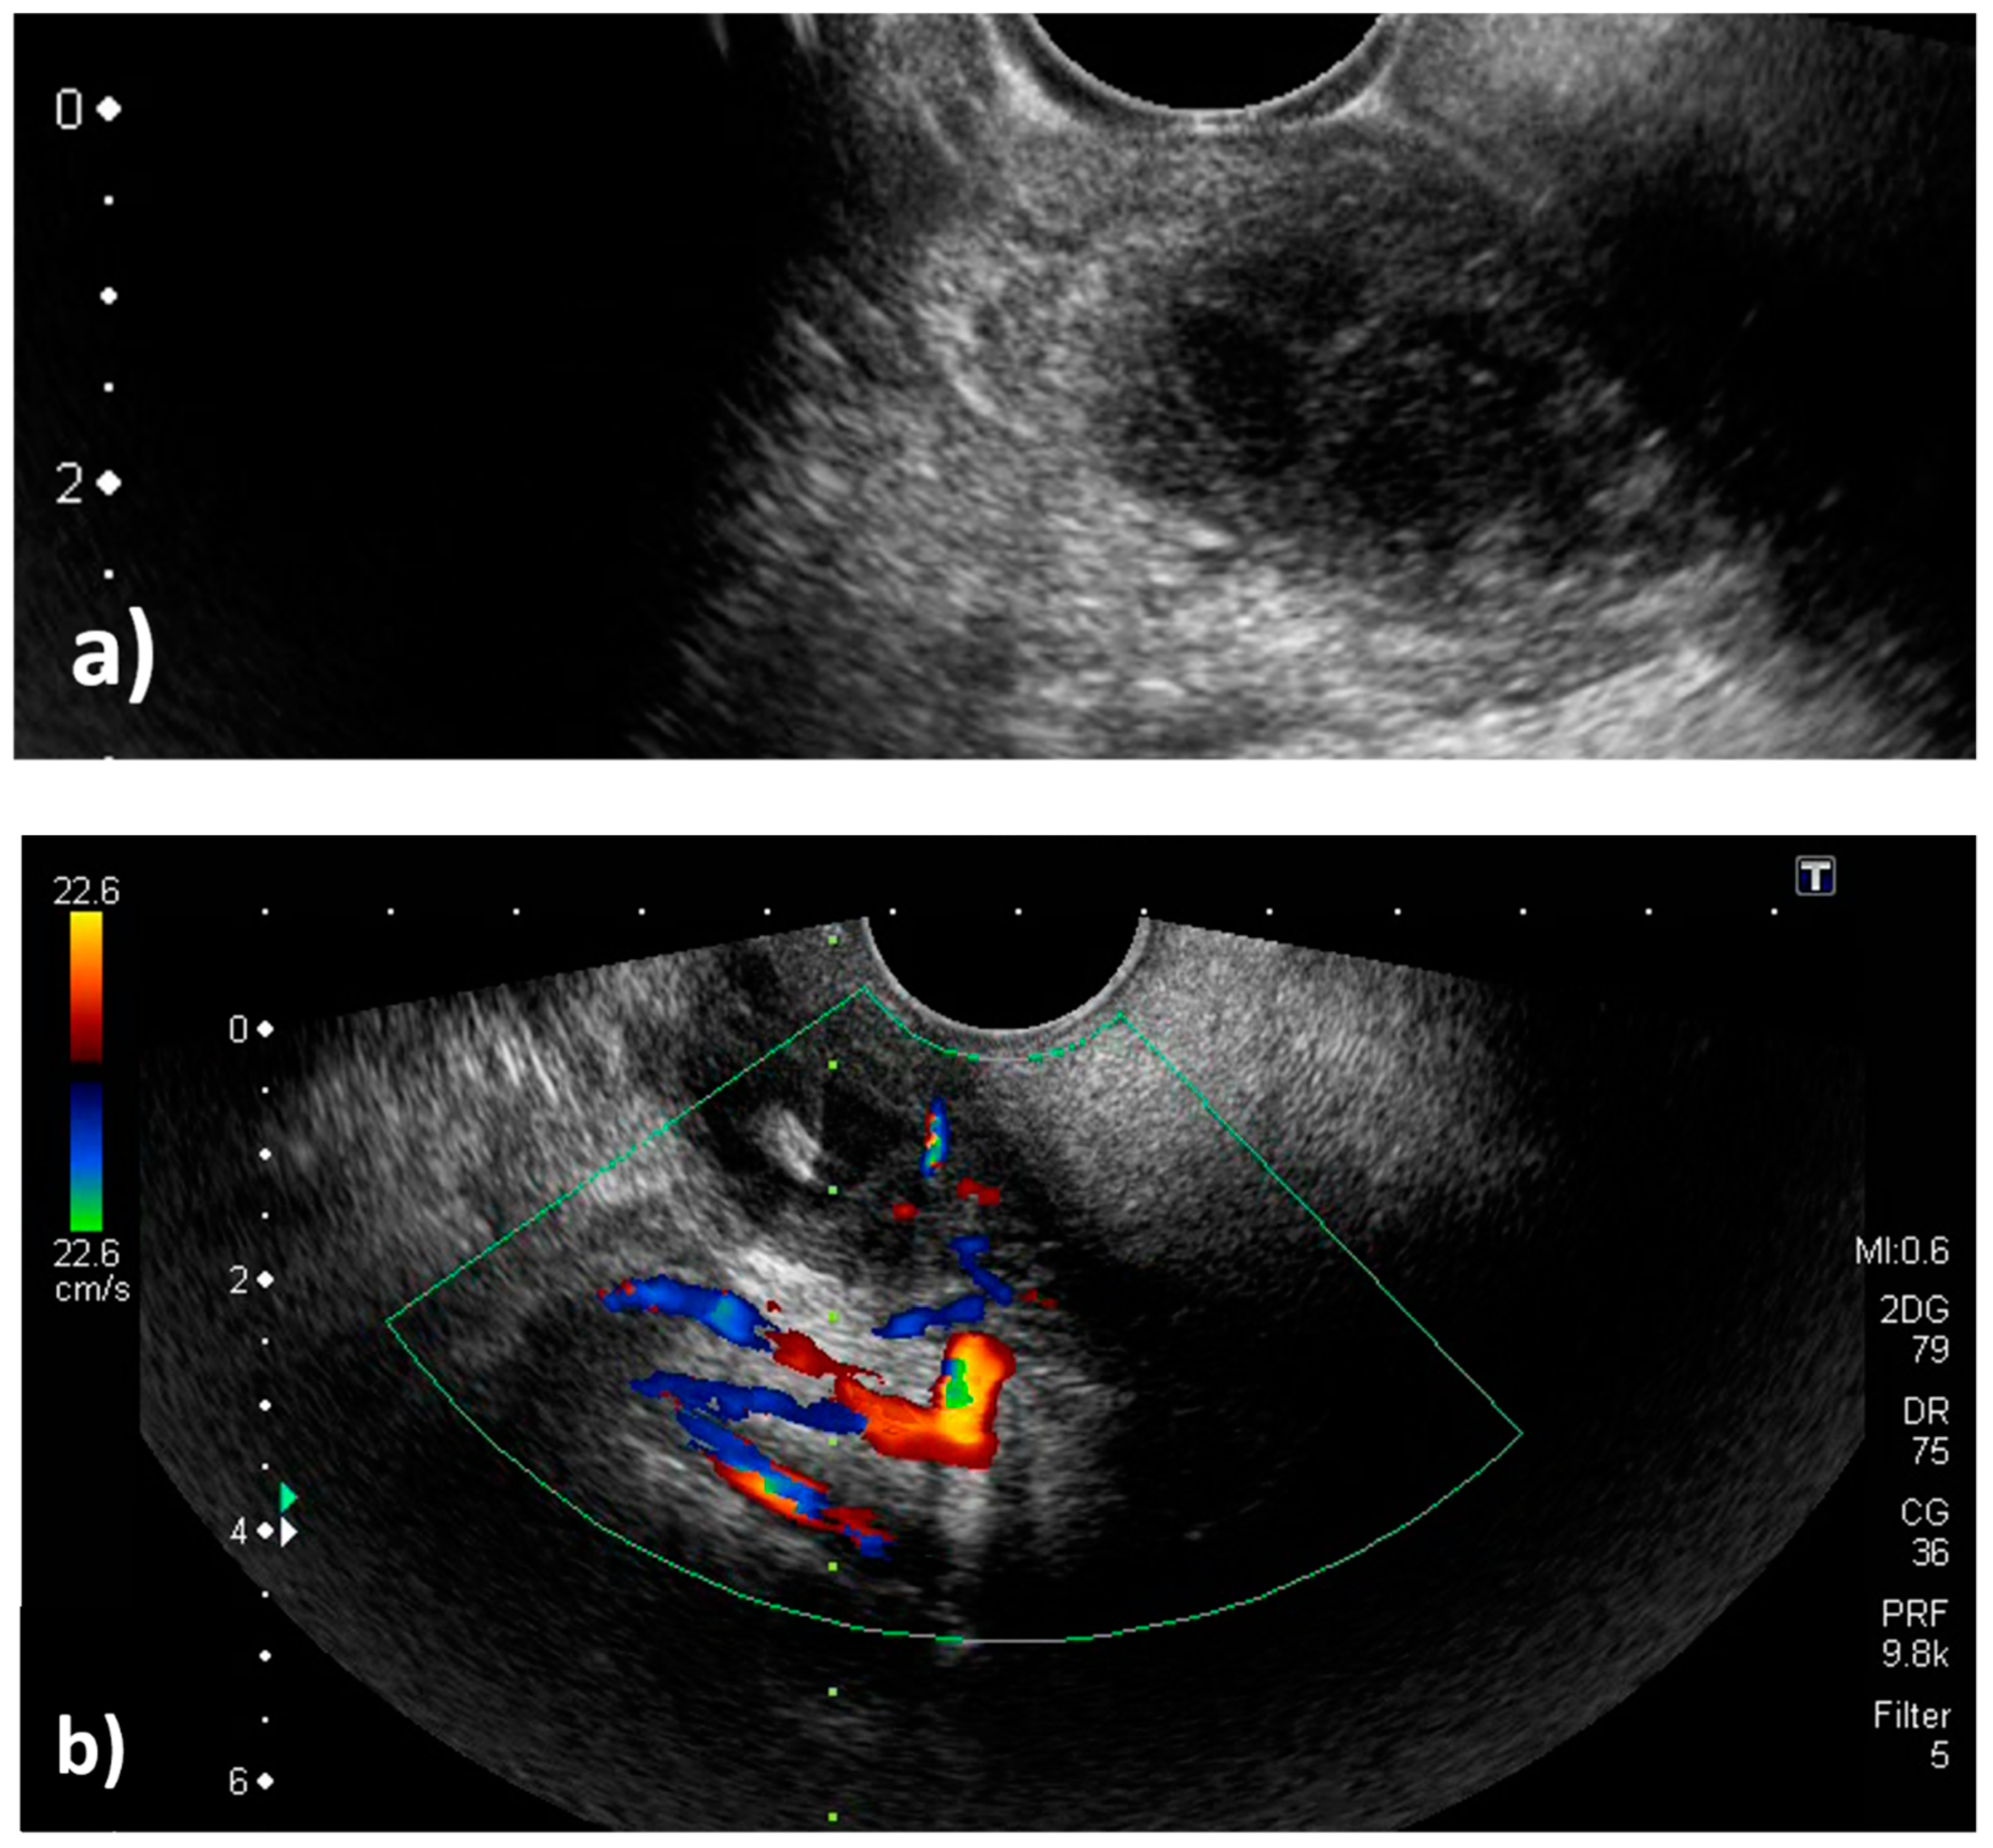

Figure 4.

Transoral pharyngeal ultrasonography (TOPU). (a) TOPU with B-mode. (b) TOPU with color Doppler. The left side of the image is the head side, and the right side is the foot side. TOPU shows the internal carotid artery (ICA) under the abscess at a depth of 30–40 mm and the external carotid artery (ECA) just under the abscess at a depth of 20–30 mm. The branches of the ECA surround the head side of the abscess. The tip of the needle is inserted at the center of the abscess in the hypoechoic space. The vertical green dotted line indicates the direction in which the needle advances; this guiding line system is incorporated in the ultrasound machine (Aplio500). (c) Schematic image. The periphery of the abscess is indicated by the red circle. It is easy to differentiate between the ICA and ECA because the branch arteries are visualized along with the ECA.